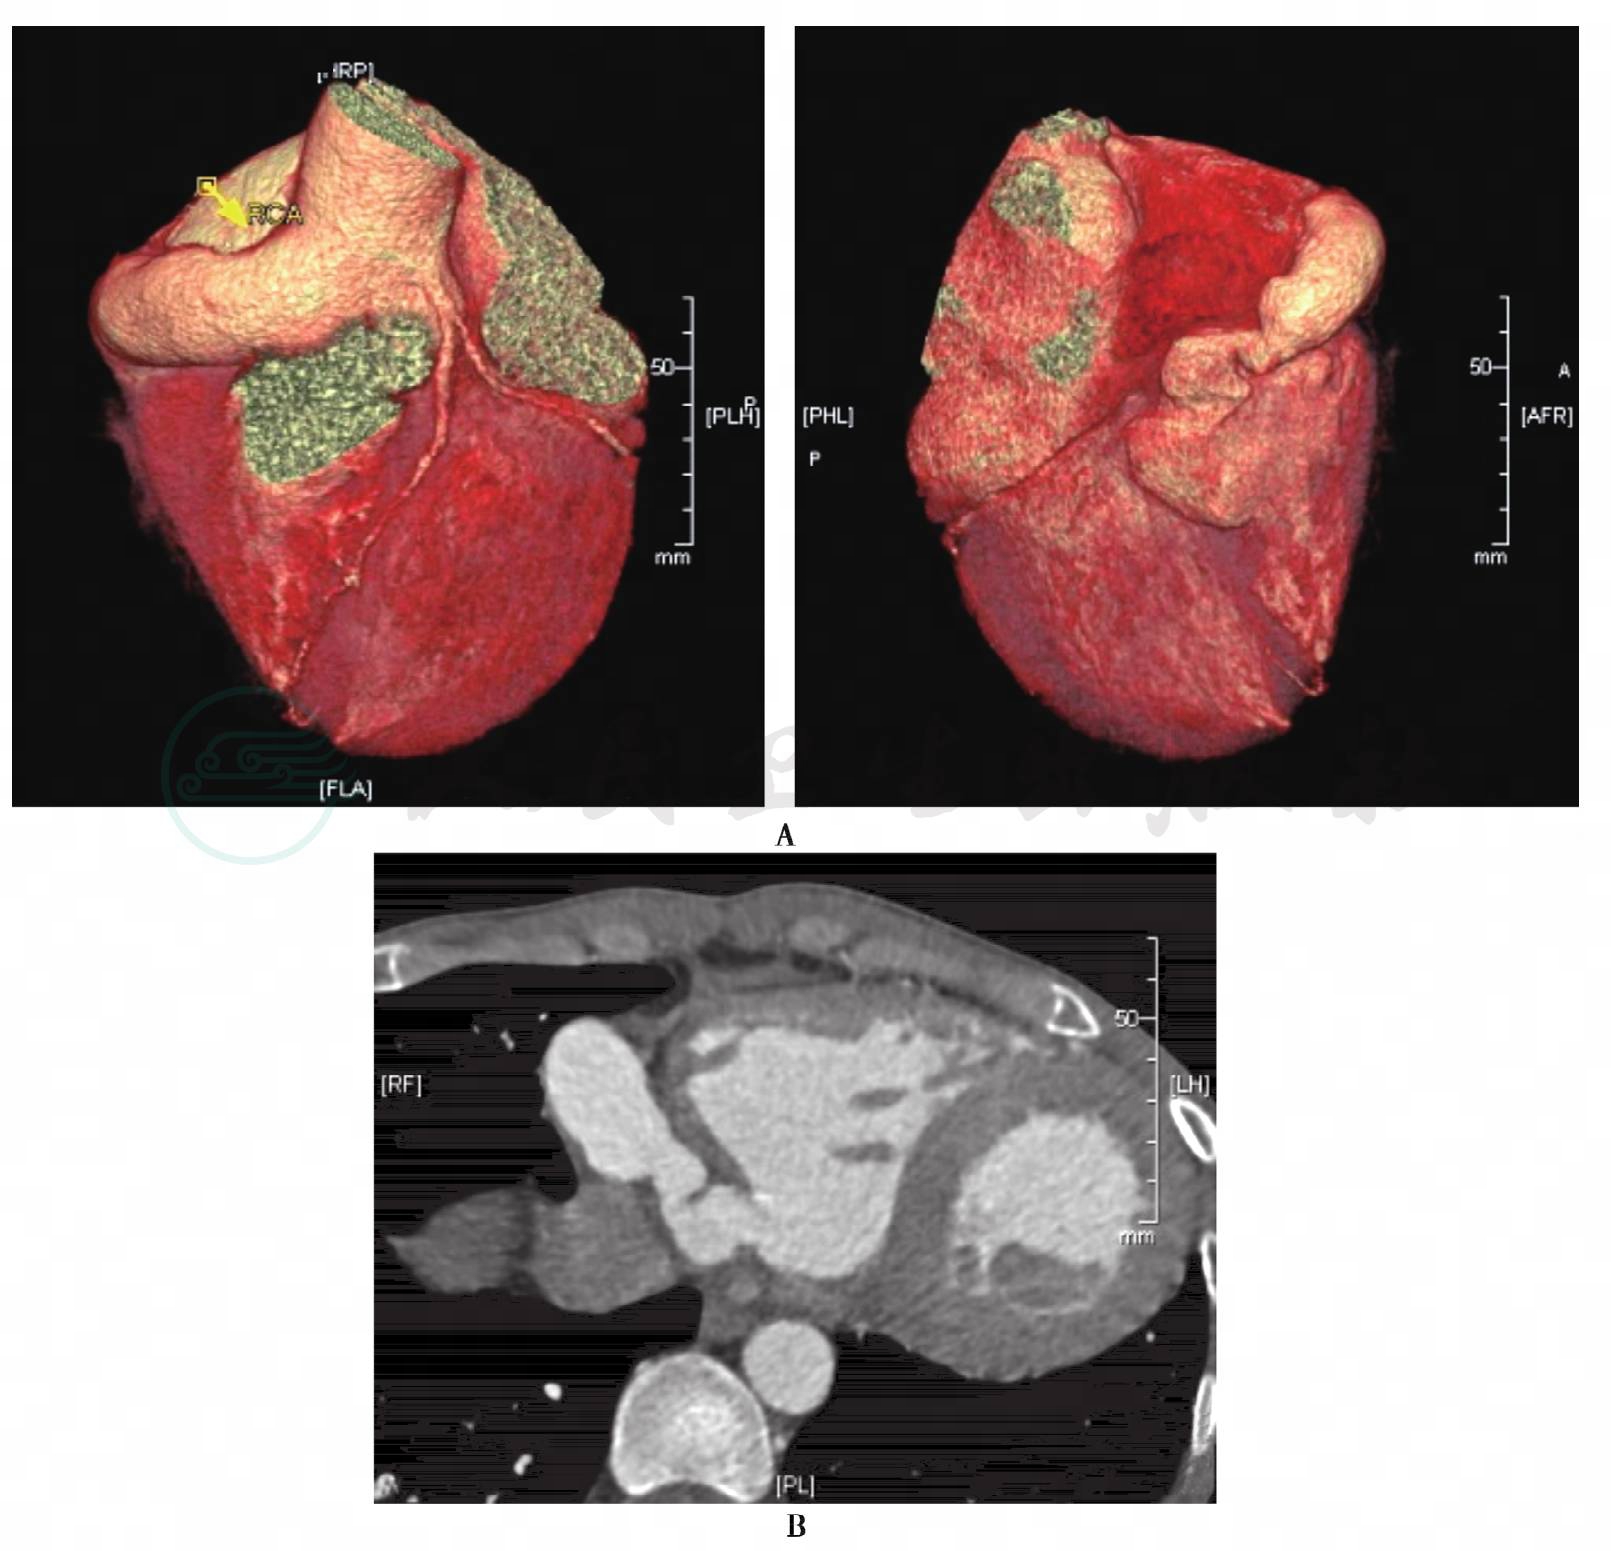

而后,进一步完善冠状动脉造影:左主干粗大,未见狭窄;前降支近中远段未见狭窄;左回旋支中等,近中远段未见狭窄;右冠状动脉自开口至远段极度扩张,显影欠佳(图2)。结论:右冠状动脉瘤样扩张,右冠状动脉-右心室瘘。左心室造影:轻度主动脉瓣反流,右冠状动脉显影且全程极度扩张,右心室延迟显影;左心室压94/8mmHg,左心室流出道压90/17mmHg。右心导管术:右心室明显扩大。冠状动脉CT重建:右冠状动脉弥漫性扩张,右冠状动脉-右心室瘘 (图3)。

图3 术前冠状动脉CT

A:容积重建显示巨大右冠动脉汇入右心室;B:二维轴位图像进一步证实右冠状动脉汇入右心室